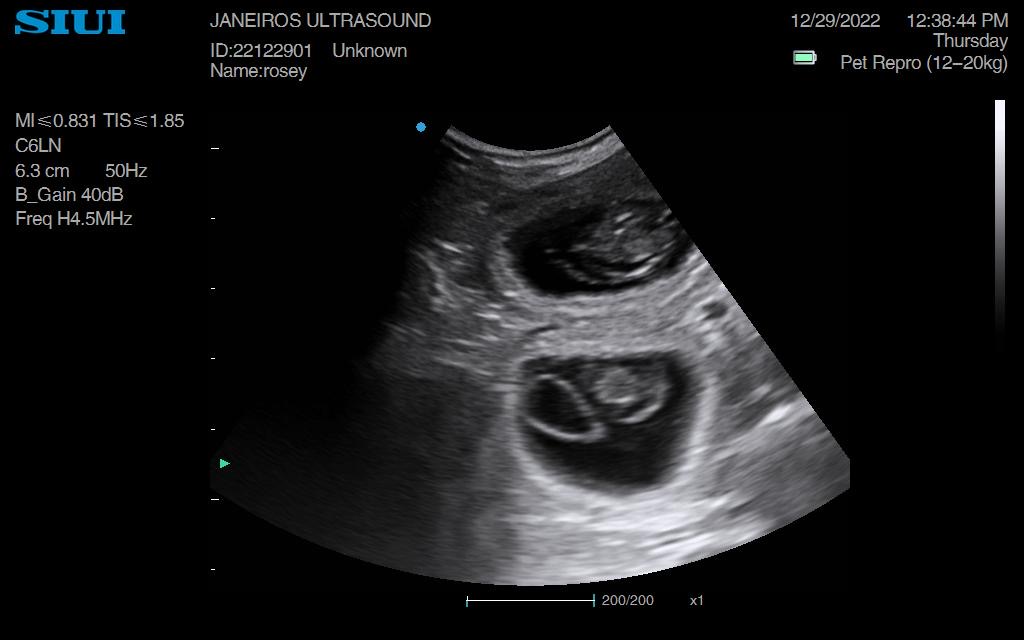

Rosey Dachshund Ultrasound Conisbrough Animal Ultrasound Association Dachshund Ultrasound The best way to determine if your dachshund is pregnant is with a blood test performed at the veterinarian. The vet should be able to determine the number of puppies your dachshund will have, as well as any potential abnormalities. The pups continue to grow during this stage. Take your dachshund to the vet for a blood test or ultrasound. Dachshund Ultrasound.

Rosey Dachshund Ultrasound Conisbrough Animal Ultrasound Association Dachshund Ultrasound Take your dachshund to the vet for a blood test or ultrasound if you suspect she is pregnant. During week 4, visit the vet once more to confirm the pregnancy through ultrasound examination. The spine and the eyes start to develop, and their faces begin to shape up. The best way to determine if your dachshund is pregnant is with. Dachshund Ultrasound.

Rosey Dachshund Ultrasound Conisbrough Animal Ultrasound Association Dachshund Ultrasound Around two to three weeks after. Your vet can perform an ultrasound to confirm the pregnancy and check the health of the embryos. At this stage, the fetuses are about the size of a. You might notice that your dog’s nipples are slightly enlarged. Ultrasound of a dachshund at approximately 33 days gestation. During week 4, visit the vet once. Dachshund Ultrasound.